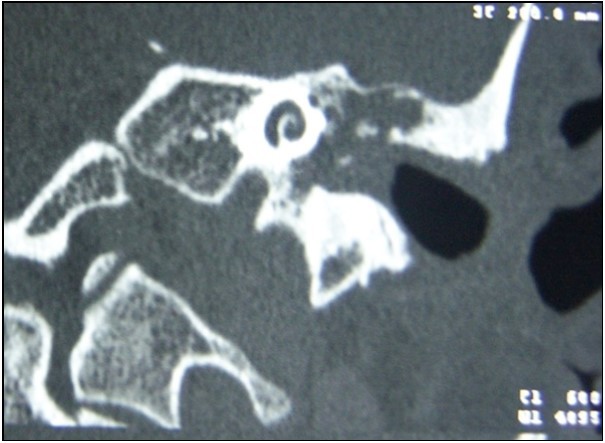

All preoperative CT scans included soft tissue in tympanic cavity, 23 (69.7%) of them demonstrated bone tissue erosion whereas 10 (30.3%) of them did not (Figure 2) (Table 1).

18 of 23 (78.3) patients who had bone erosions on CT images were observed to have cholesteatoma intraoperatively while the remaining 5 (21.7) were not. Cholesteatoma was detected in 7 of 10 (70%) patients who did not have any sign of bone destruction on CT and remaining 3 (30%) of them were negative (Table 2). No significant result was obtained in terms of impact of tomographic view of bone erosions on indicating presence of intraoperative cholesteatoma (p=0,61)

Figure 2.Soft tissue image causing bone erosion on temporal CT